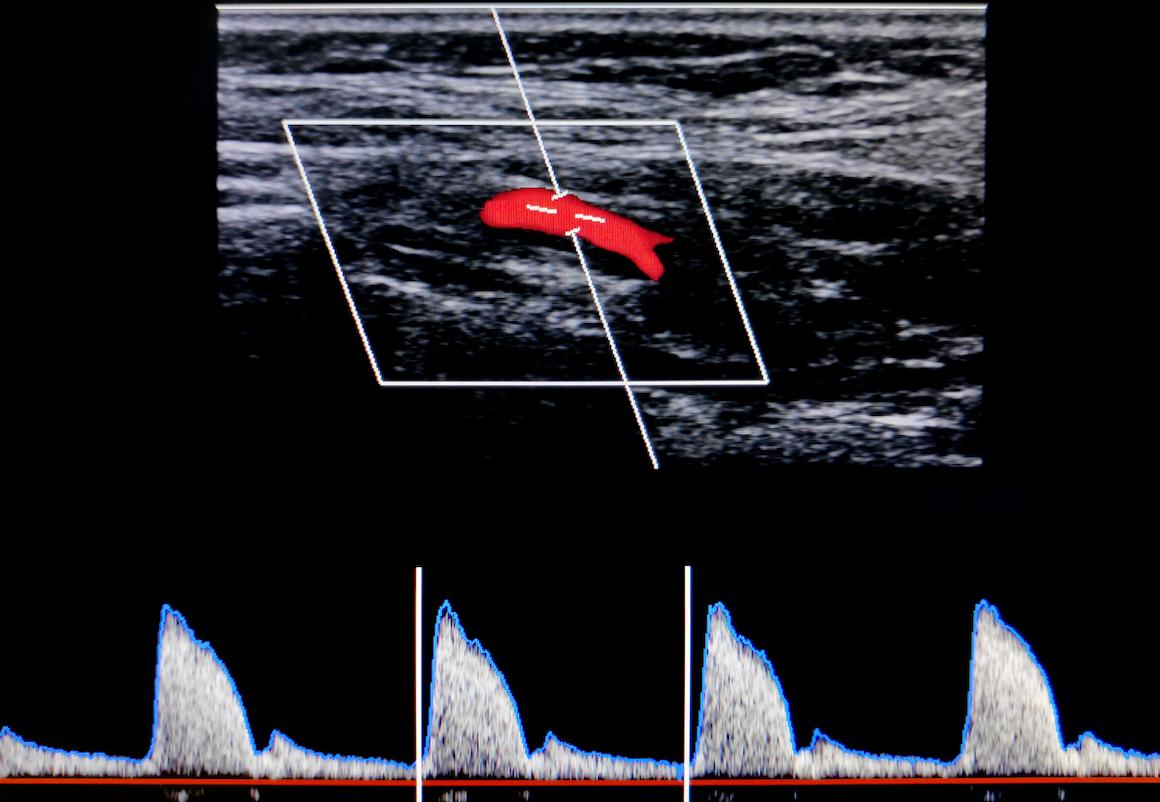

- kalus/istock

Selon les auteurs, ces résultats appellent à reconsidérer le recours systématique à la revascularisation carotidienne chez les patients à risque faible ou intermédiaire, privilégiant un traitement médical optimisé rigoureux. De futures études devraient explorer l'intérêt de l'imagerie spécifique (IRM carotidienne avec recherche d'hémorragie intra-plaque) pour affiner davantage l'évaluation individuelle du risque et préciser les sous-groupes qui bénéficieraient réellement d'une revascularisation.